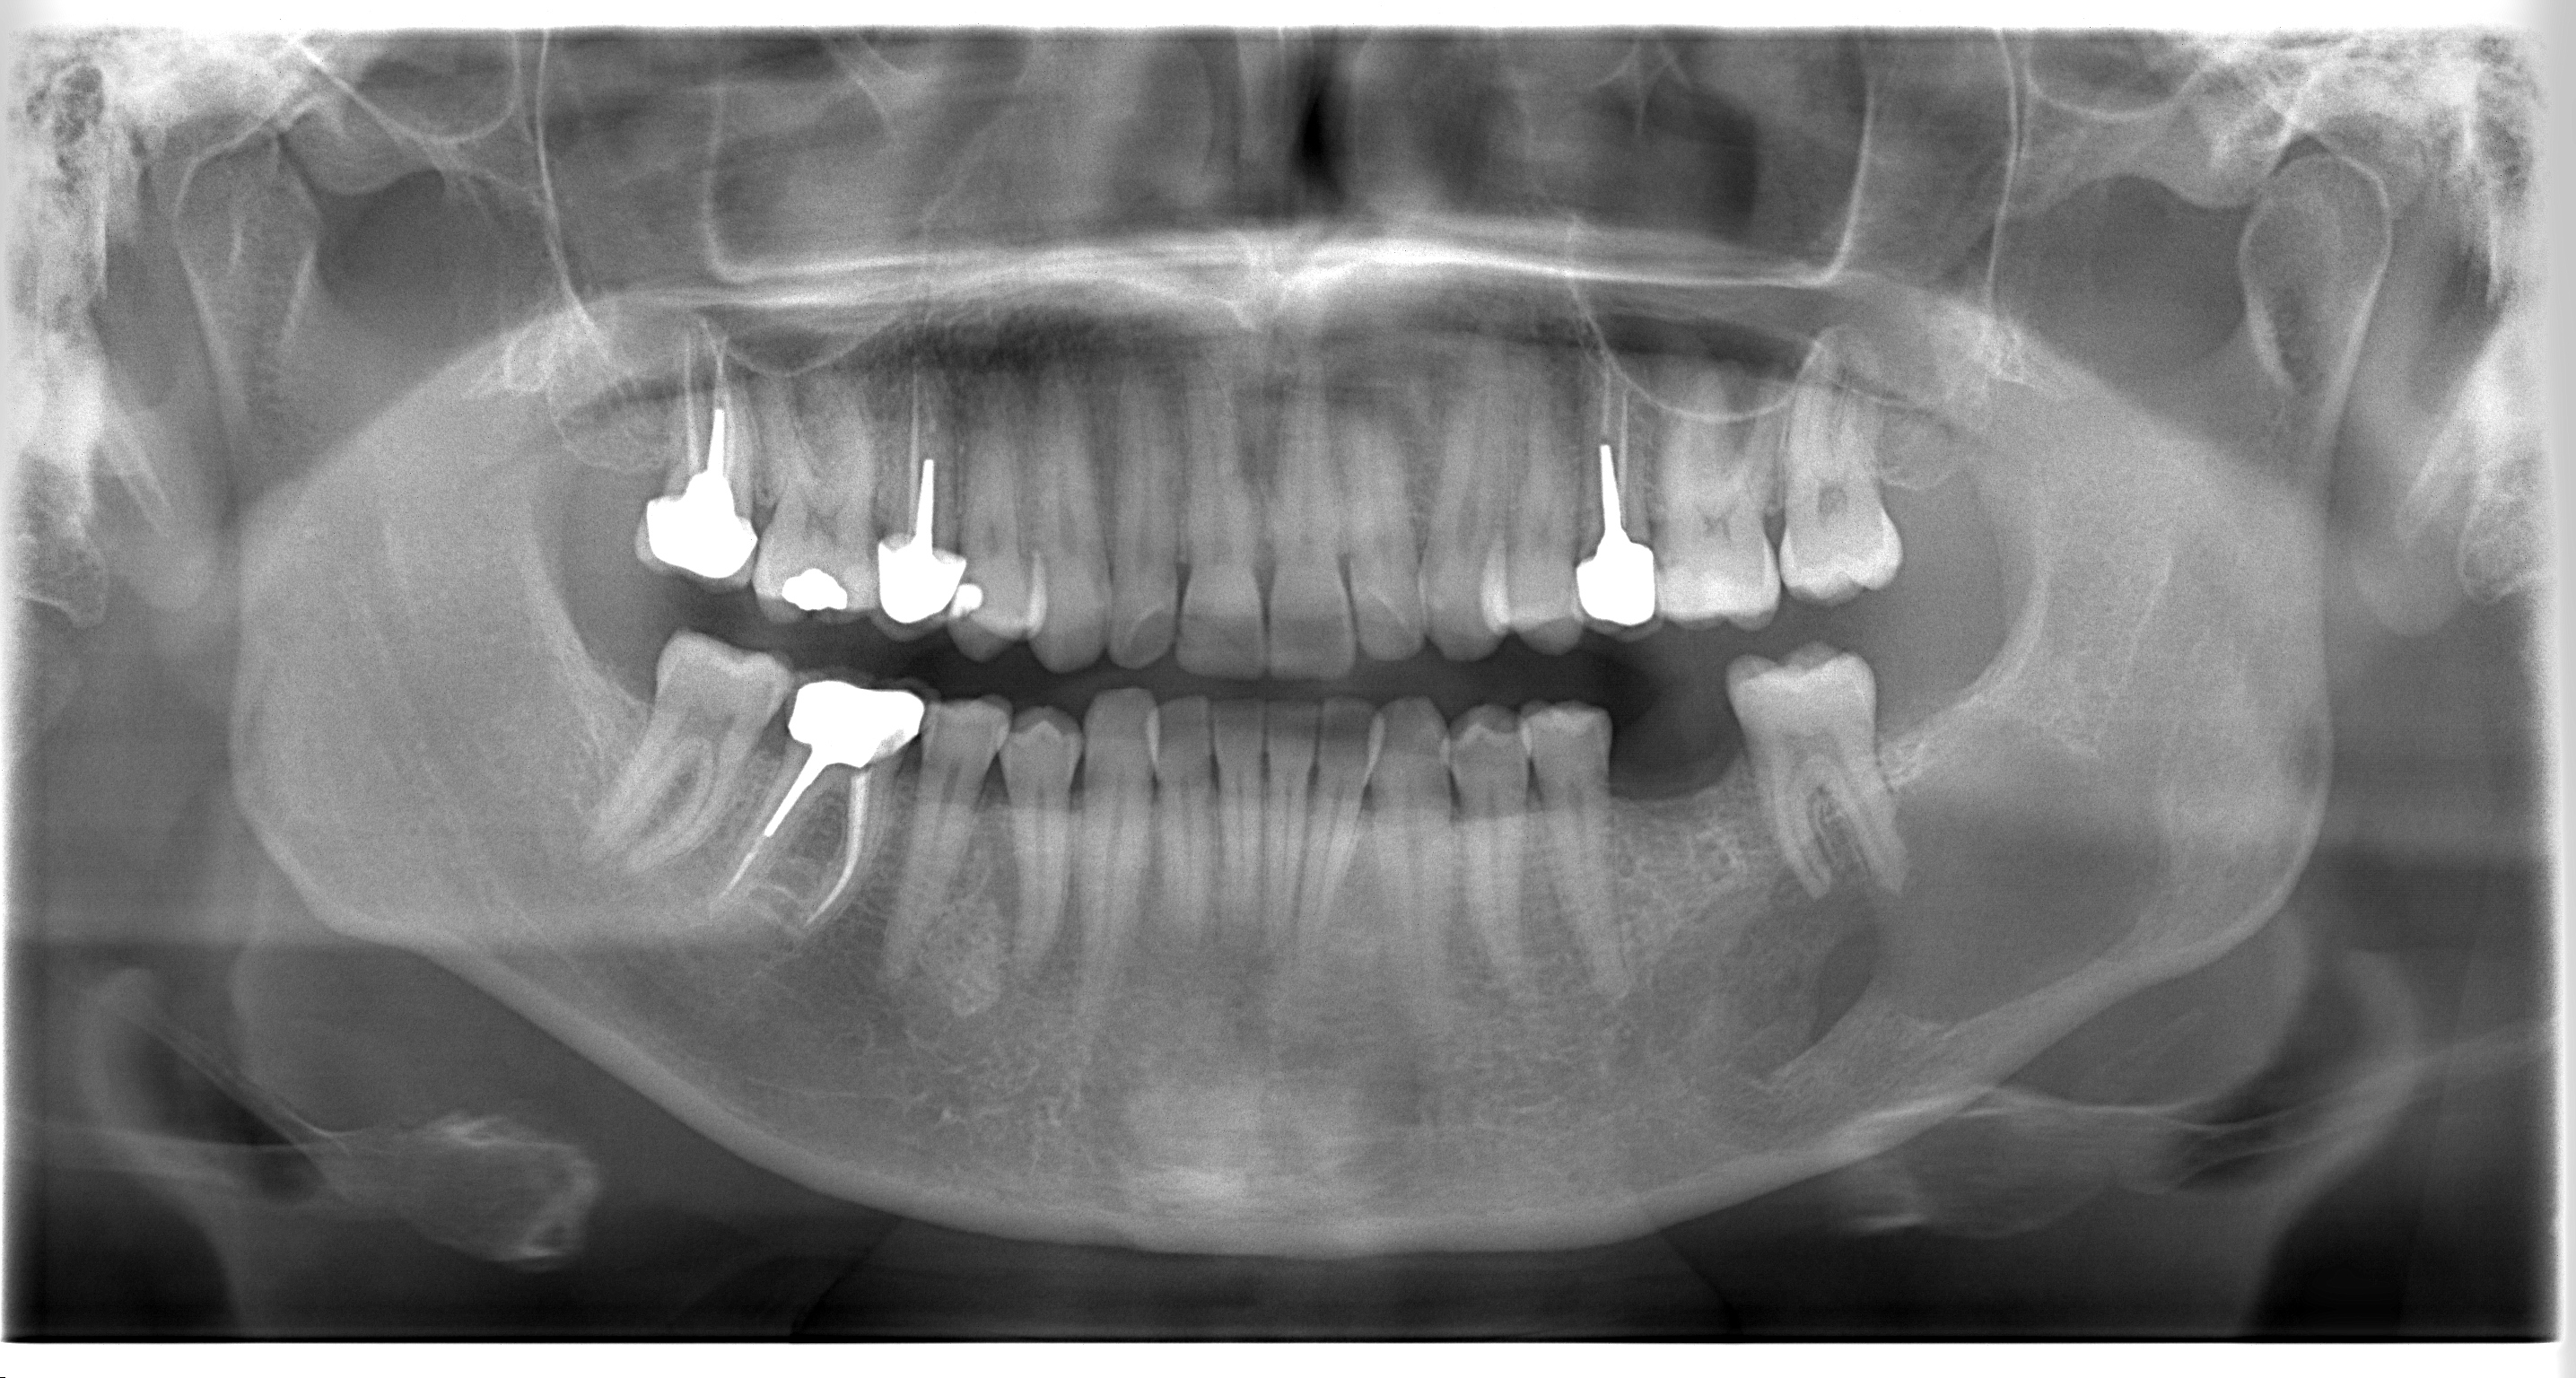

Le 3 Avril 2025 se déroulera notre A.E.U RADIO-ANATOMIE DENTO-MAXILLAIRE

Objectifs:

- Compléter ses connaissances acquises par l’actualisation des bases.

- Augmenter sa compétence par l’acquisition de nouvelles connaissances.

- Organiser l’analyse des images, par une stratégie de recherche visuelle.